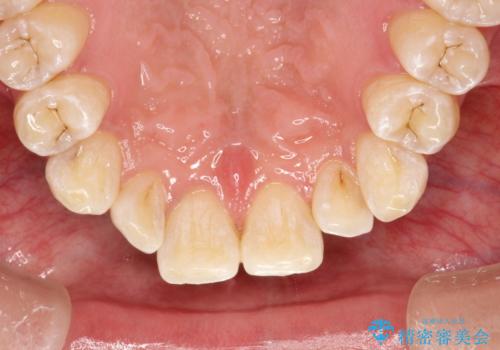

- 歯磨きの際に出血したり、口臭も気になるとのことで来院されました。PMTC30分コースにてクリーニングを行いました。